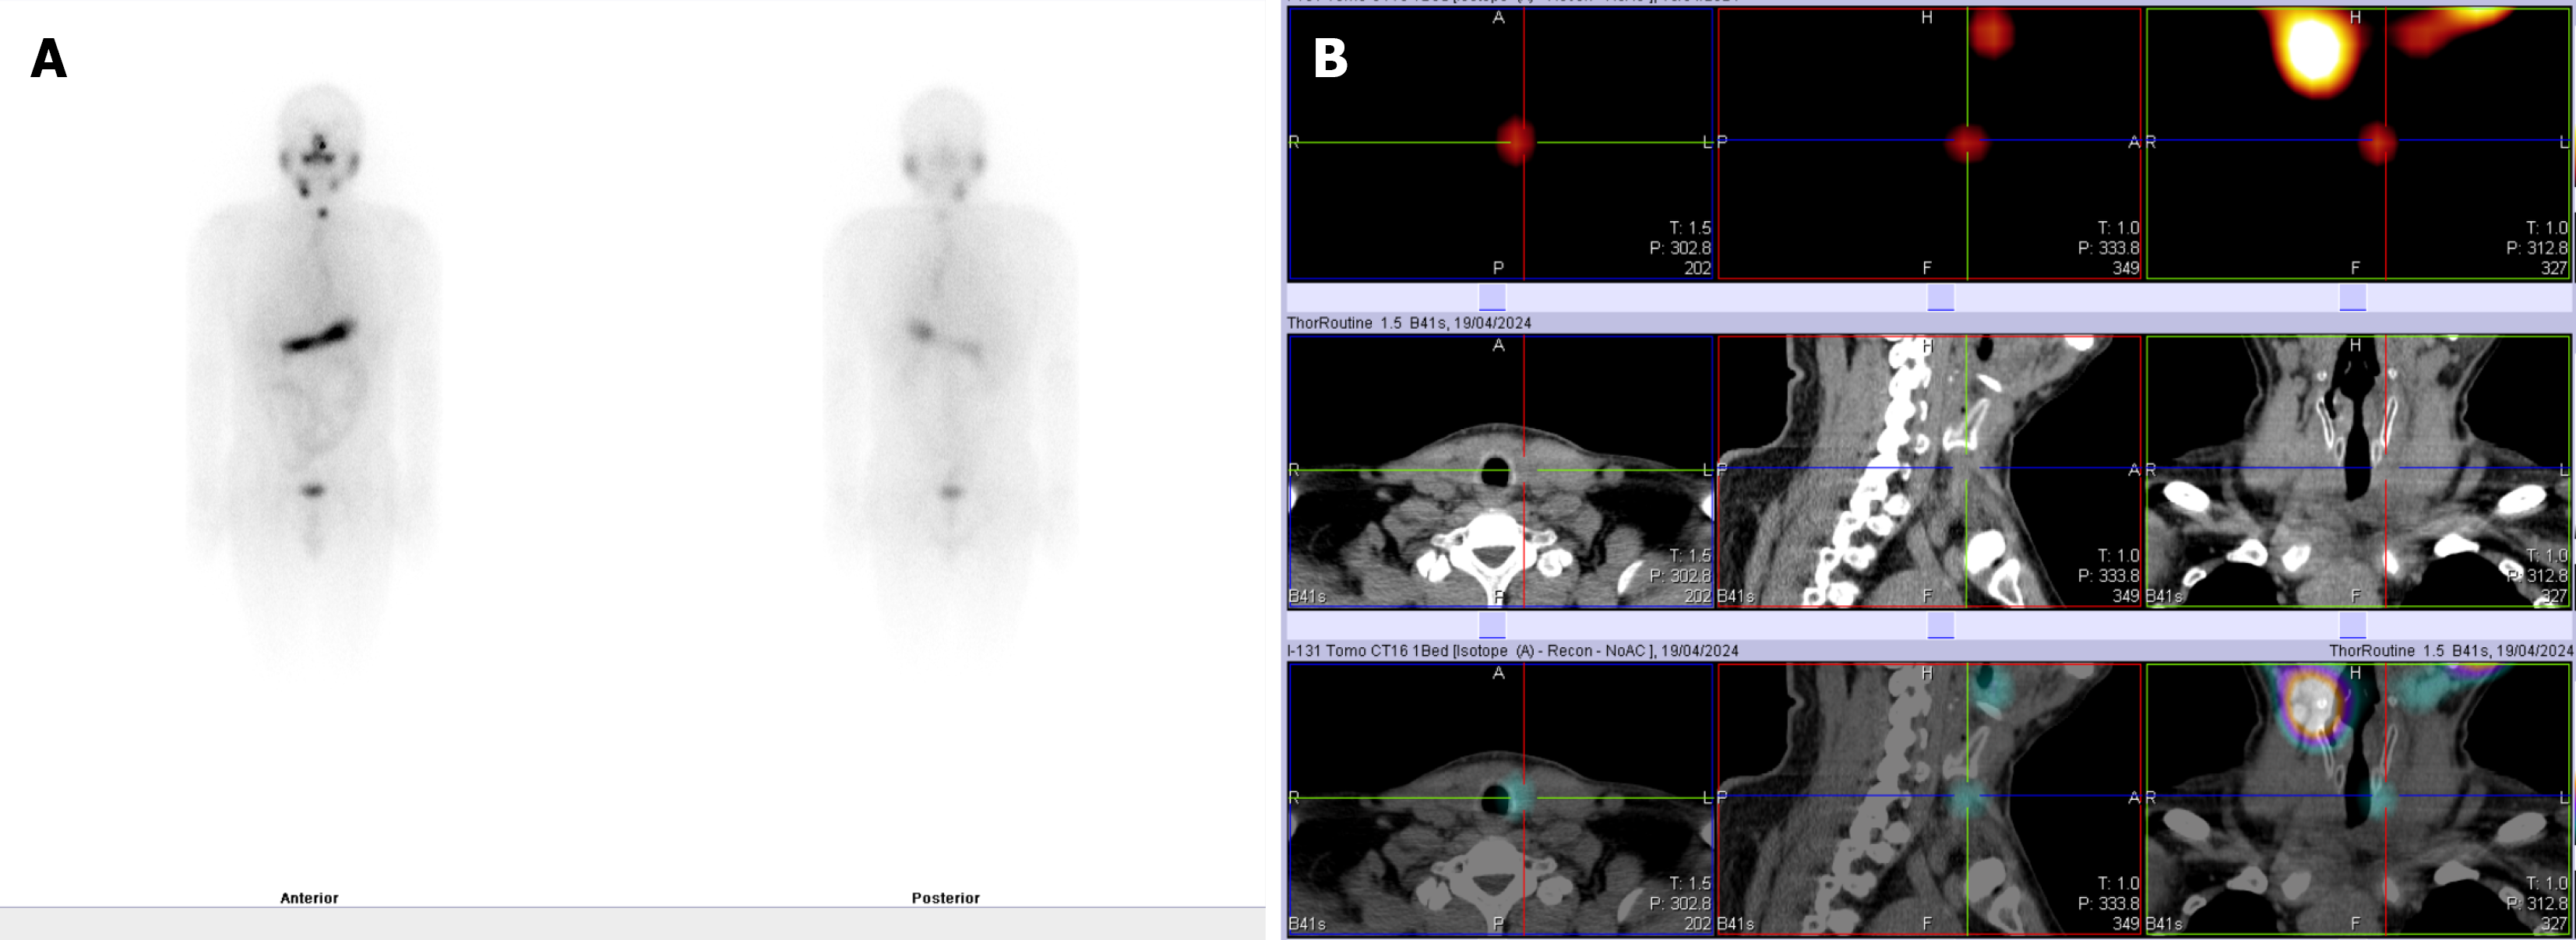

Postoperatively, the patient’s heart rate and blood pressure remained stable, and there were no significant abnormalities in diet or gastrointestinal function. He patient experienced transient hypoparathyroidism, which was treated with calcium supplements for five days. Subsequent parathyroid hormone and serum calcium levels returned to normal. The patient received radioactive iodine (I-131) treatment and TSH suppression therapy postoperatively (Figure 7).

After I-131 therapy, follow-up tests showed thyroid globulin (TG1) at 4.31 ng/mL and TSH at 0.29 mIU/L.Regular outpatient follow-up was conducted at 3 months, 6 months, and 1 year postoperatively. Fiberoptic laryngoscopy indicated persistent left vocal cord paralysis. However, the patient’s voice quality (timbre) and pitch significantly improved compared to their preoperative state.